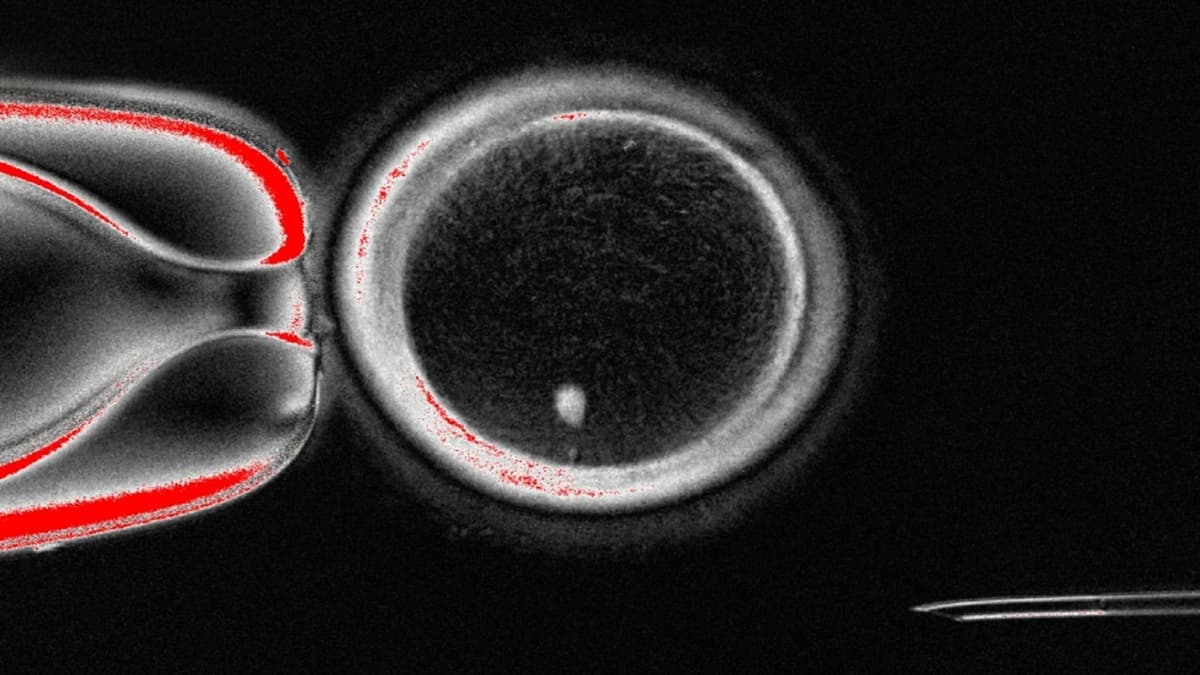

Mereka menciptakan metode pembelahan sel baru yang dinamakan mitomeiosis, gabungan antara proses mitosis dan meiosis. Dengan teknik somatic cell nuclear transfer, inti sel kulit dimasukkan ke dalam sel telur donor yang sudah dikosongkan, sehingga inti sel tersebut membuang setengah kromosom layaknya meiosis dan menghasilkan sel telur haploid.

Dalam penelitian ini, sebanyak 82 sel telur fungsional dibuat dan dibuahi dengan sperma. Walaupun sebagian besar embrio mengalami gangguan kromosom dan berhenti berkembang di tahap awal, sekitar 9 persen berhasil mencapai tahap blastokista pada hari keenam setelah fertilisasi.